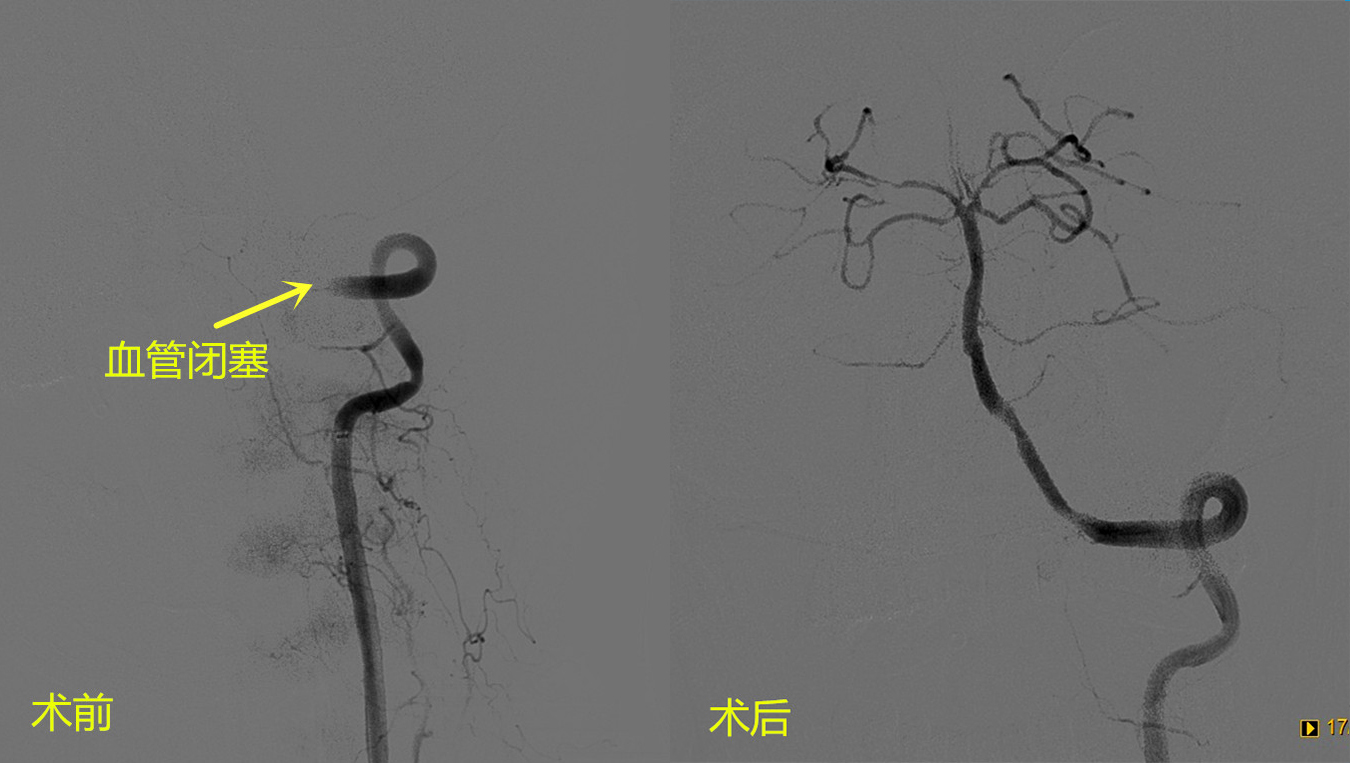

1月18日,67岁的陈女士因“发作性眩晕、复视5天,精神不振、左侧肢体无力2小时”,紧急到我院就诊,诊断脑干、小脑多发梗死。因发病时间长,错过静脉溶栓机会,病情逐渐加重,医生决定进行动脉取栓治疗。患者脑血管造影显示供应脑干、小脑的椎-基底动脉完全闭塞,如果不及时开通堵塞血管,病情继续发展,可出现昏迷,四肢瘫痪,甚至生命危险。因为病变处血管解剖结构复杂,而且存在椎动脉颅内段动脉硬化闭塞,远端存在血栓,所以手术风险高、难度大。

王克水主任和许业宦主治医师首先用球囊扩张闭塞血管,然后将血栓抽吸出来,最后在闭塞段放置一枚支架,血管完全开通,术后第2天陈女士的症状全部消失。